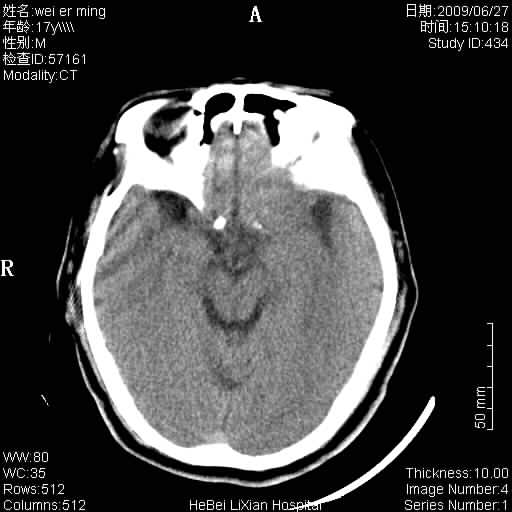

标题: CT20838:帮忙看看,是软化灶吗?

患者,男,67岁.既往有脑血栓病史.若是软化灶里面怎么出现钙化呢?

脑软化灶伴灶内钙化,钙化可能是梗塞后出血,出血钙化.

支持软化灶伴穿通畸形,钙化为胶质增生、机化、钙化。

支持 右侧额叶软化灶伴脑穿通畸形(钙化为胶质增生、机化、钙化)。

是脑软化灶,其内的钙化可解释为闭塞血管内的血栓钙化。

脑梗塞后形成的软化灶内可以有钙化密度影,系血管出血机化或血管内血栓钙化所致。